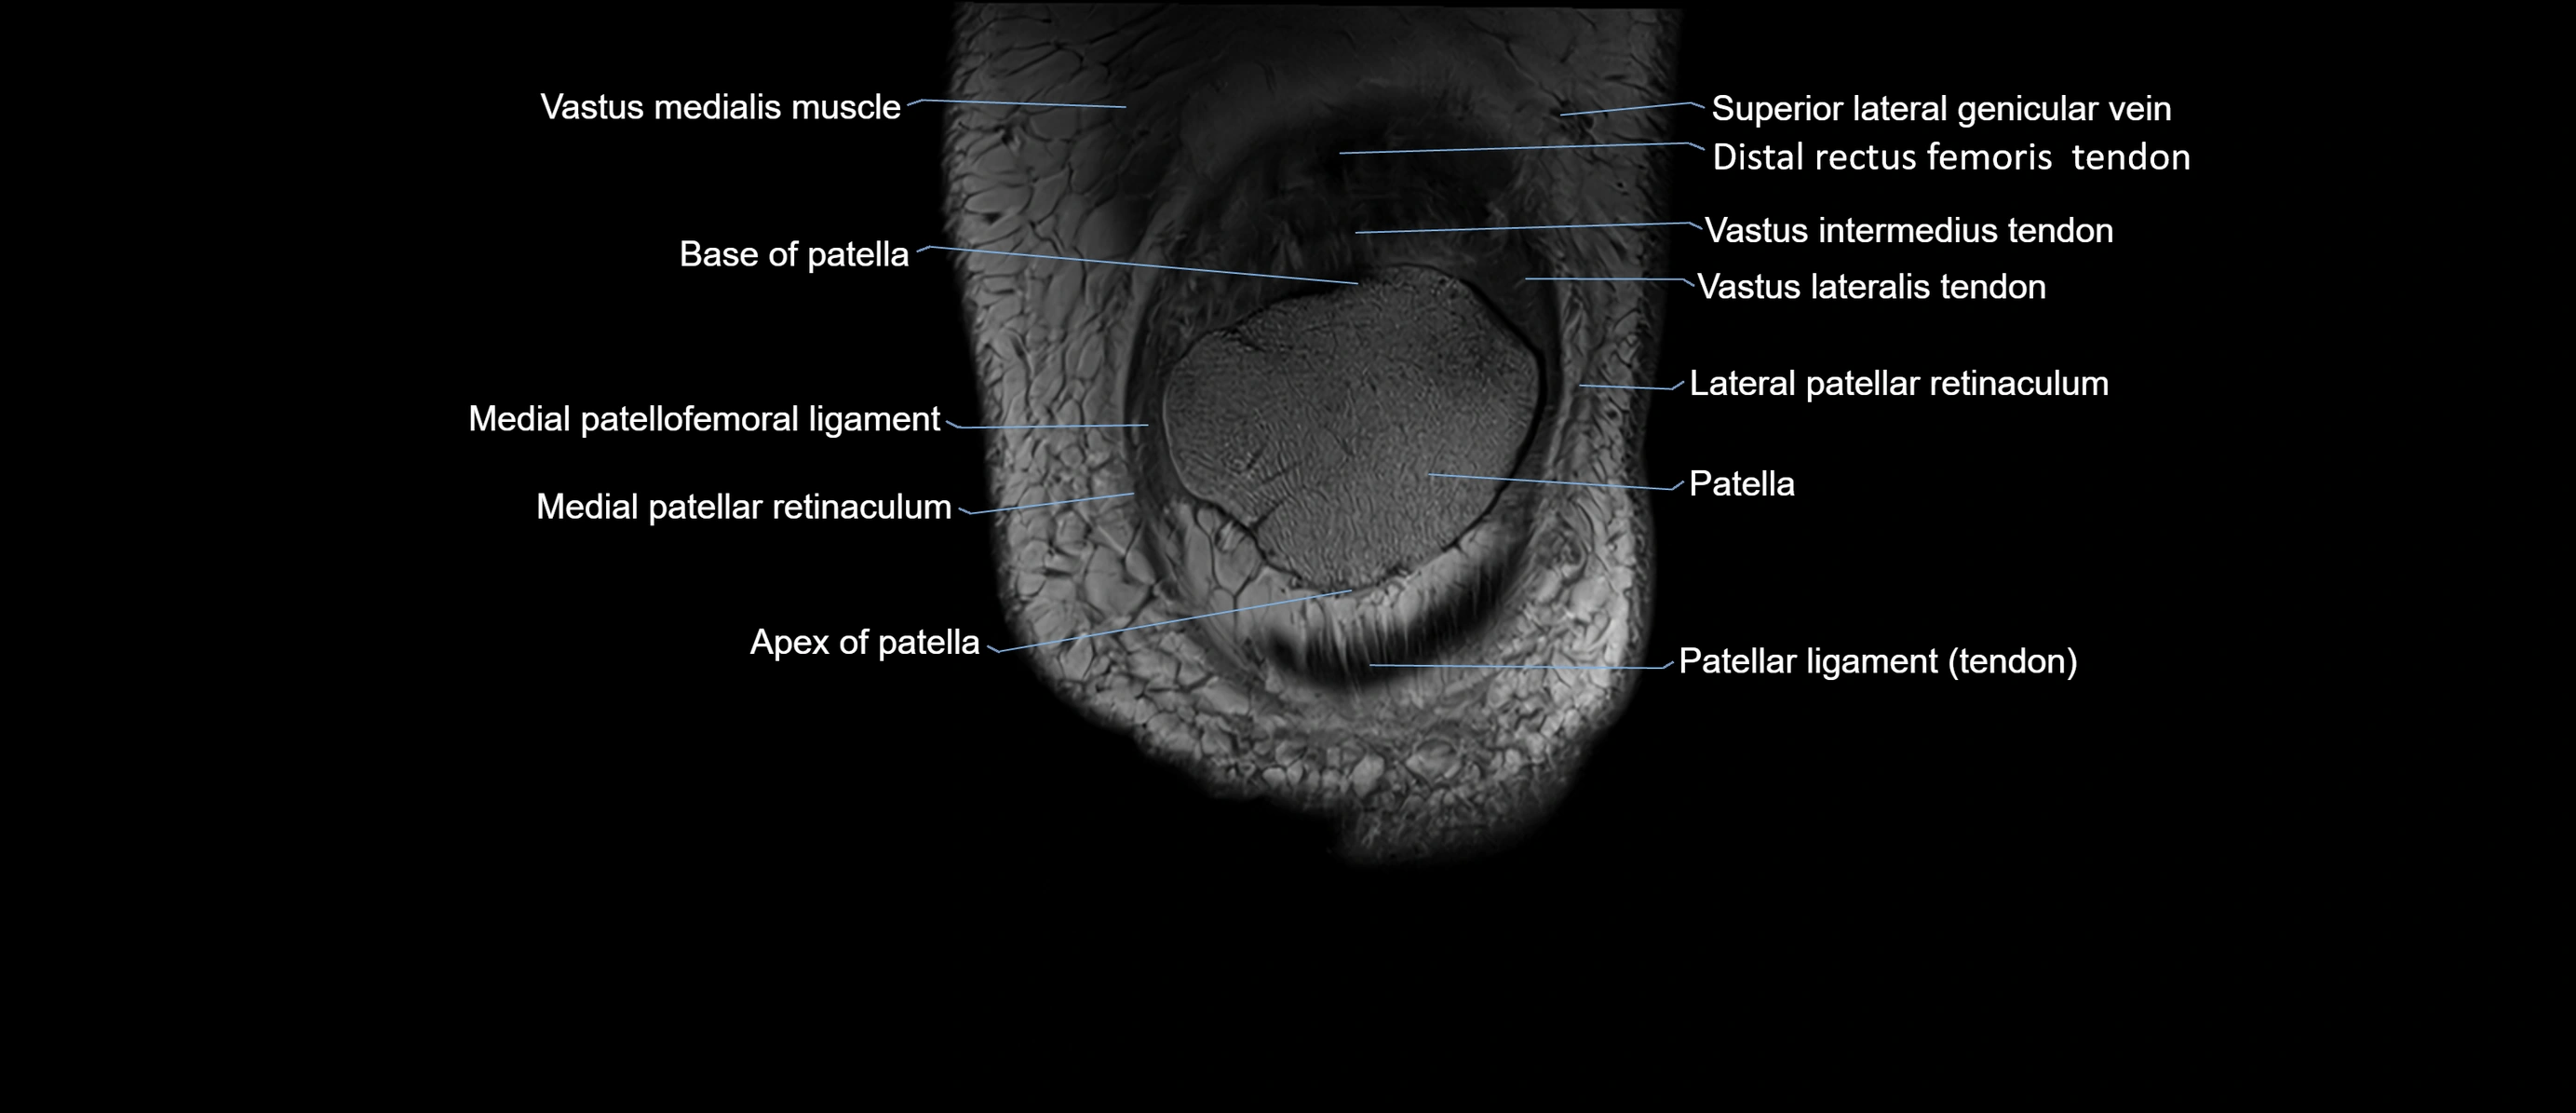

- Base of patella

- Distal rectus femoris tendon

- Distal vastus intermedius tendon

- Distal vastus lateralis tendon

- Lateral patellar retinaculum

- Medial patellar retinaculum

- Medial patellofemoral ligament

- Patella

- Patellar articular cartilage

- Patellar tendon (patellar ligament)